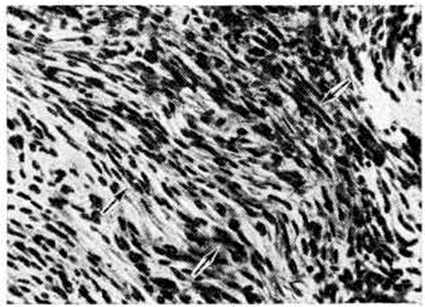

МенингиомаМенингиома (meningioma, греческий meninx, meningos мозговая оболочка + -oma; синонимы: грибовидная опухоль твёрдой мозговой оболочки, фиброэндотелиома, менинготелиома, арахноидэндотелиома, арахноидальная менингиома, менингеальная фибробластома, менингобластома) — внемозговая, в большинстве случаев доброкачественная опухоль, исходящая из твёрдой, реже мягкой оболочки головного или спинного мозга, редко из сосудистого сплетения мозговых желудочков или возникающая эктопически в костях черепа, позвоночника и по ходу нервных корешков. По локализации различают: 1. Менингиома оболочек головного мозга: 1) конвекситальную; 2) парасагиттальную — встречается вдоль угла, образованного стенкой верхнего продольного синуса и твёрдой мозговой оболочкой выпуклой поверхности больших полушарий; может сдавливать синус или врастать в него; 3) большого серповидного отростка; 4) тенториальную; 5) твёрдой мозговой оболочки основания мозга: а) передней черепной ямки — ольфакторной ямки, бугорка турецкого седла; б) средней черепной ямки — крыльев основной кости; в) задней черепной ямки — блюменбахова ската, края большого затылочного отверстия. 2. Менингиома оболочек спинного мозга. 3. Внутрижелудочковую Менингиома, исходящую из сосудистого сплетения. 4. Экстрадуральную Менингиома — исходит из наружных слоёв твёрдой мозговой оболочки, часто инфильтрирует прилежащие кости черепа, стенки позвоночного канала. Менингиома, связанные с оболочками зрительного нерва, располагаются в зрительном канале, в полости орбиты. 5. Эктопическую Менингиома—встречается в костях черепа и позвоночника, в придаточных полостях носа, в полостях внутреннего и среднего уха, по ходу нервных корешков. Микроскопически Менингиома обычно представляет собой хорошо отграниченный узел округлой или полдовоидной формы (рисунок 1), нередко спаянный с внутренней поверхностью твёрдой мозговой оболочки. Встречаются и плоские узлы. Спинальная Менингиома чаще продолговатая, при экстрадуральном расположении может муфтой охватывать дуральный мешок. По величине Менингиома варьируют в диаметре от нескольких миллиметров до 15 сантиметров и более. Консистенция Менингиома довольно плотная, особенно при обилии фиброзной ткани. В большинстве случаев опухоль окружена плотной капсулой. На разрезе ткань Менингиома серо или мясо-красная, при обильном содержании так называемый ксантомных клеток принимает охряную окраску. Наличие кист в Менингиома не характерно. Менингиома обычно одиночны, но могут быть и множественные. В редких случаях множественная Менингиома сочетается с множественной невриномой — болезнь Реклингхаузена (смотри полный свод знаний Нейрофиброматоз). Гистологический классификации Менингиома не отличаются существенно одна от другой. Согласно гистологической классификации опухолей центральная нервная система, принятой Комиссией ВОЗ по опухолям мозга (Женева, 1976), выделяются следующие подтипы Менингиома: Менинготелиоматозная Менингиома (эндотелиоматозная, синцитиальная, арахноидэндотелиоматозная). Состоит из мозаикоподобно-расположенных мономорфных клеток с овальным или округлым ядром, содержащим умеренное количество нежных зёрен хроматина. Строма представлена немногочисленными сосудами и редкими тонкими тяжами соединительной ткани, окаймляющими клеточные поля. Характерны, но не всегда встречаются концентрические структуры, подобные разрезанной луковице, из наслаивающихся одна на другую уплощённых опухолевых клеток. Гиалинизированный центр такой структуры нередко обызвествляется (так называемый псаммомное тельце). Фиброзная Менингиома (Фибробластическая). Построена из фибробластоподобных клеток, которые располагаются параллельно друг другу и складываются в переплетающиеся между собой пучки, содержащие соединительнотканные волокна (рисунок 2). Ядра клеток вытянутые. Могут встретиться концентрические структуры, псаммомные тельца. Переходная Менингиома (смешанная). Включает структуры менинготелиоматозной и фиброзной Менингиома Псаммоматозная Менингиома — менинготелиоматозная или фиброзная Менингиома с большим количеством псаммомных телец. |

Рис. 2. | ||